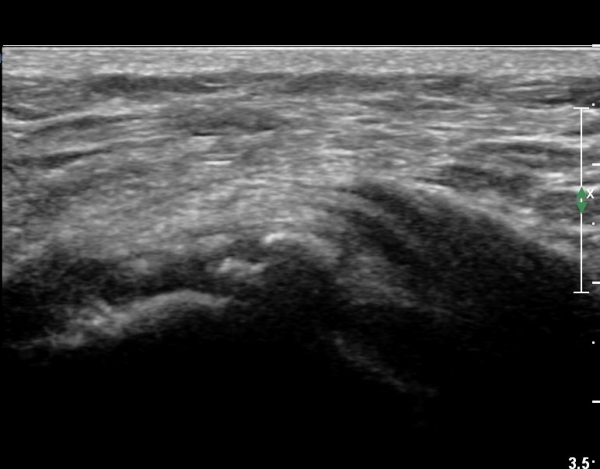

ÃÊÀ½ÆÄ °Ë»ç

Ä¡·á

Á¡¾×³¶³» ÁÖ»çÄ¡·á¿Í ¼®È¸ÀÇ ÁÖ»ç¹Ù´Ã ÀÚ±Ø(needling)